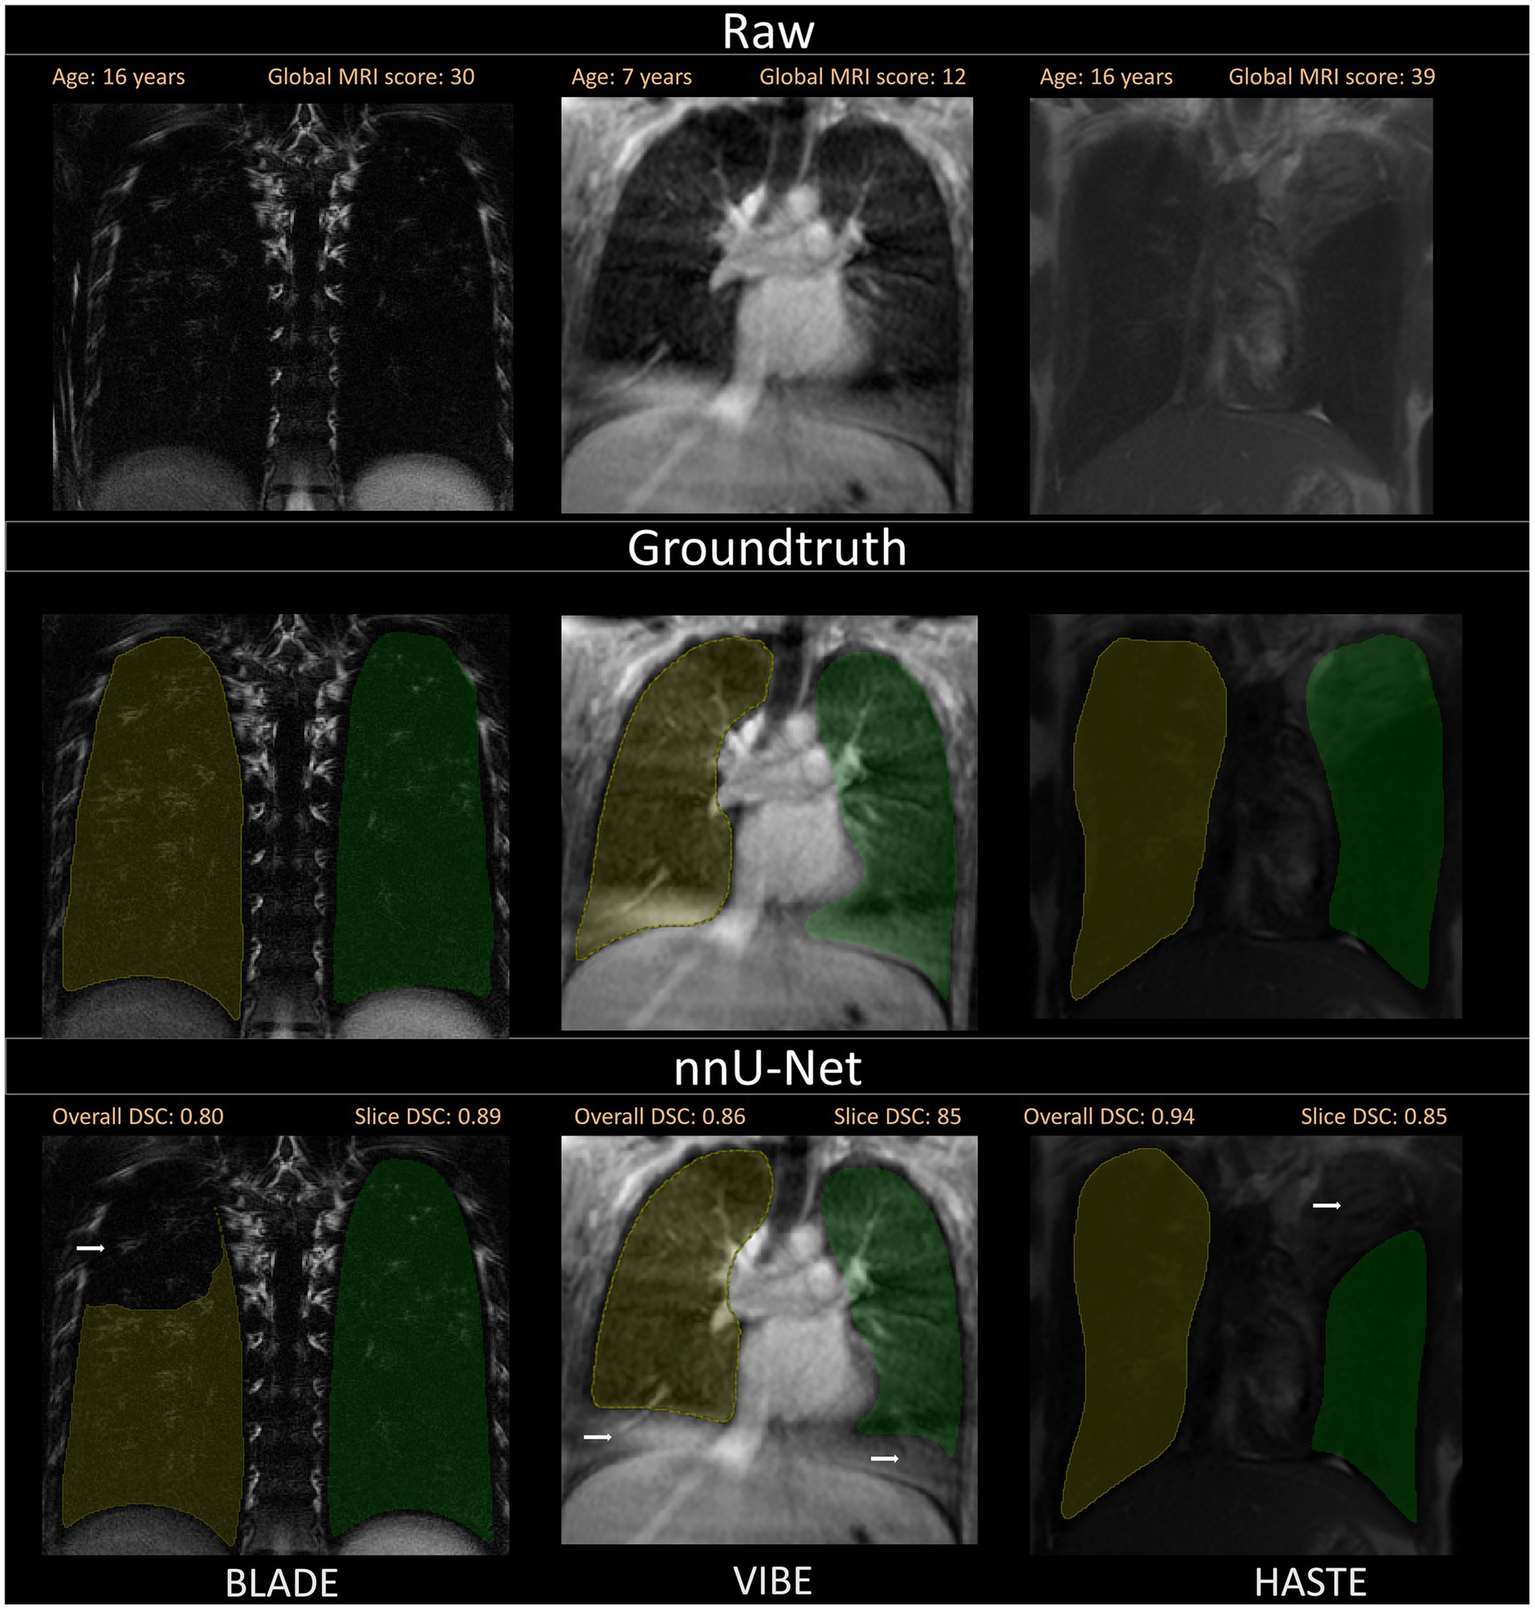

Figure 4

Visualization of the three different sequences with ground truth segmentations and good segmentations produced by the nnU-Net. Overall DSC corresponds to the dice coefficient of the entire lung and Slice DSC to the dice coefficient of the visualized slice. The segmentation of the right lung is indicated in yellow and the left lung segmentation in green. Each column corresponds to one MRI sequence. In the top row, the raw images are shown. The second row contains the manually annotated lung halves (ground truth). In the third row, the segmentation calculated by the corresponding nnU-Net is depicted. The three shown patients are of ascending age from left to right, thus the different lung sizes. All three patients have a global MRI score of 3. The results of the questionnaire indicated that the lungs were rated with a score of 10/10 for BLADE, 9/10 for VIBE, and 9/10 for HASTE. The different contrasts and gray levels are due to the different sequences. Both the ground truth and the segmentation of the lung halves appear to be very similar. Although the right and left lung differ in size and shape, segmentation performance seems to be almost equal. In general, the high Sørensen-Dice-Score and corresponding high segmentation performance are evident.

A selection of segmentations with a slightly lower Sørensen-Dice-Score, as well as visual discrepancies between ground truth and nnU-Net segmentation is shown. Overall DSC corresponds to the dice coefficient of the entire lung and Slice DSC to the dice coefficient of the visualized slice. Segmentation errors are indicated with white arrows in the second row. Three common segmentation mistakes are shown: Incomplete segmentations for BLADE, wrong segmentations due to breathing motion or other artifacts for VIBE and pathological changes influencing segmentation performance on the patient captured with the HASTE protocol. Based on the results of the questionnaire, the lungs were rated with a score of 2/10 for BLADE, 6/10 for VIBE, and 7/10 for HASTE.